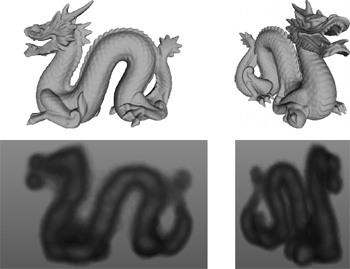

F. P. Vidal, P.-F. Villard, and É. Lutton.

Tuning of patient specific deformable models using an adaptive

evolutionary optimization strategy.

IEEE Transactions on Biomedical Engineering, 59(10):2942-2949,

October 2012.

F. P. Vidal, P.-F. Villard, and É. Lutton.

Tuning of patient specific deformable models using an adaptive

evolutionary optimization strategy.

IEEE Transactions on Biomedical Engineering, 59(10):2942-2949,

October 2012.

We present and analyze the behavior of an evolutionary algorithm designed to estimate the parameters of a complex organ behavior model. The model is adaptable to account for patients specificities. The aim is to finely tune the model to be accurately adapted to various real patient datasets. It can then be embedded, for example, in high fidelity simulations of the human physiology. We present here an application focused on respiration modeling. The algorithm is automatic and adaptive. A compound fitness function has been designed to take into account for various quantities that have to be minimized. The algorithm efficiency is experimentally analyzed on several real test-cases: i) three patient datasets have been acquired with the breath hold protocol, and ii) two datasets corresponds to 4D CT scans. Its performance is compared with two traditional methods (downhill simplex and conjugate gradient descent), a random search and a basic realvalued genetic algorithm. The results show that our evolutionary scheme provides more significantly stable and accurate results. Keywords: Evolutionary computation, inverse problems, medical simulation, adaptive algorithm |

| [13] |

This paper is an overview of a method recently published in a biomedical journal (IEEE Transactions on Biomedical Engineering, http://tbme.embs.org). The method is based on an optimisation technique called “evolutionary strategy” and it has been designed to estimate the parameters of a complex 15-D respiration model. This model is adaptable to account for patient's specificities. The aim of the optimisation algorithm is to finely tune the model so that it accurately fits real patient datasets. The final results can then be embedded, for example, in high fidelity simulations of the human physiology. Our algorithm is fully automatic and adaptive. A compound fitness function has been designed to take into account for various quantities that have to be minimised (here topological errors of the liver and the diaphragm geometries). The performance our implementation is compared with two traditional methods (downhill simplex and conjugate gradient descent), a random search and a basic real-valued genetic algorithm. It shows that our evolutionary scheme provides results that are significantly more stable and accurate than the other tested methods. The approach is relatively generic and can be easily adapted to other complex parametrisation problems when ground truth data is available. Keywords: Evolutionary computation, inverse problems, medical simulation, adaptive algorithm |